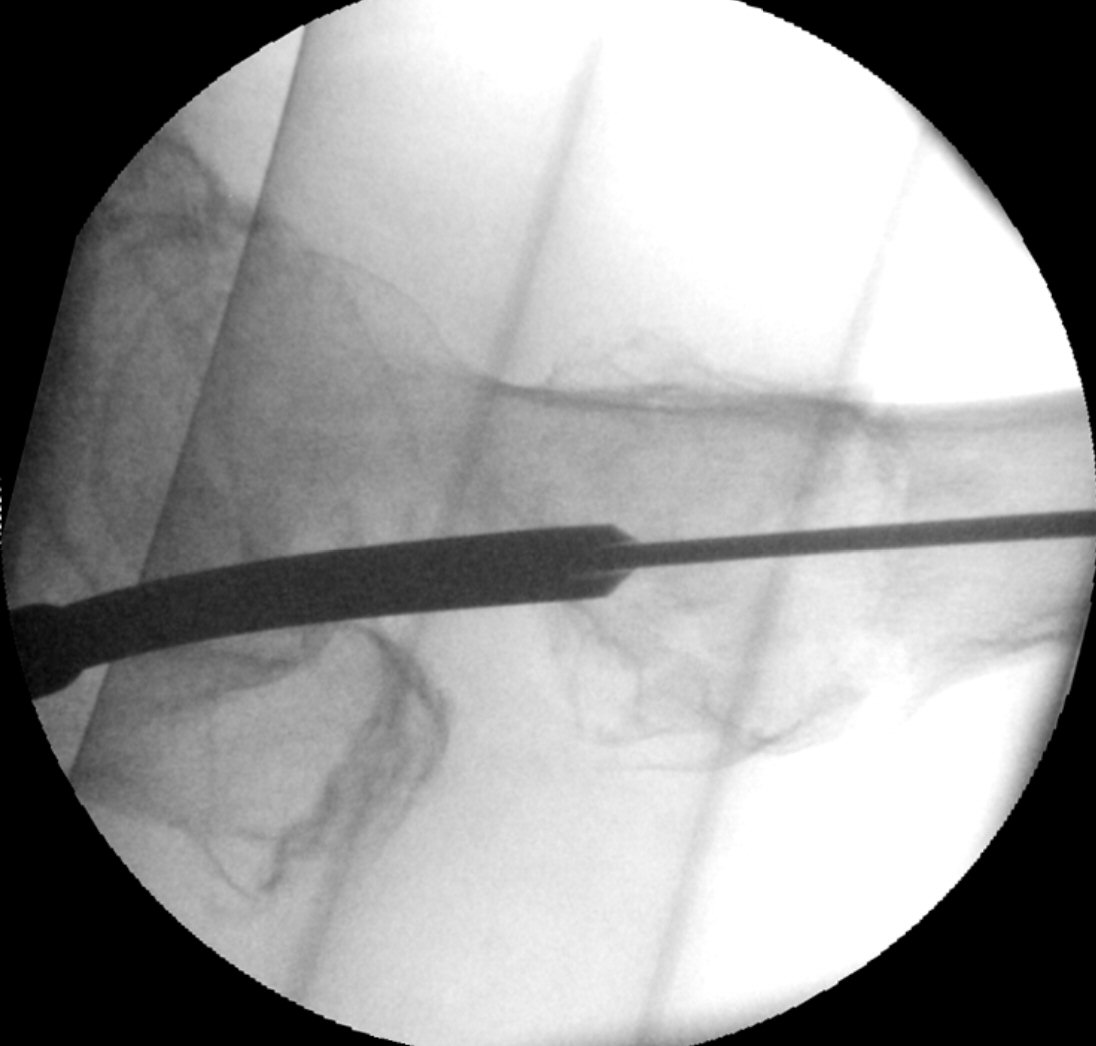

- Sätt på glidskruvens guide och mät med plastmallen "One shot device" så att spiken kommer lagom långt in, glidskruven ska hamna lite distalt om kaputs centrum i frontalvy.

Frontalbild, mall i genomlysning